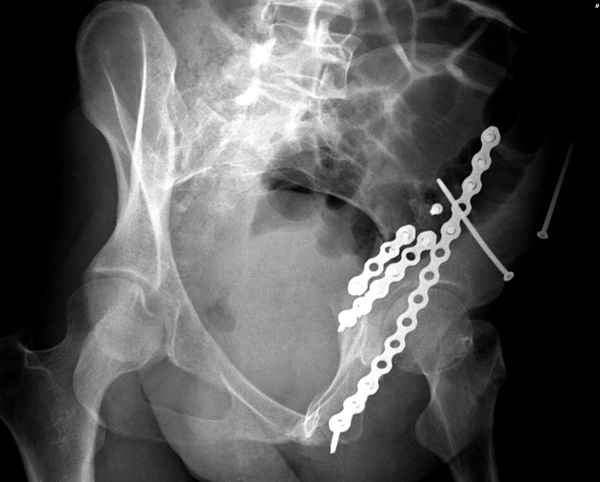

Из того минимума, что представлено, мне кажется, мы имеем дело с двухколонным переломом вертлужной впадины. Обычно медиальный (центральный) "вывих" головки встречаются в сложных двухколонных переломах со смещением.

По-моему, надо готовить больного к будущей артропластике, но без опоры на задний столб невозможно удержать протез. Опорная конструкция (кольца и т.д.) должны иметь опору, и поэтому мы бы сделали реостеосинтез задним доступом. При надобности остеотомия и рутинная фиксация с межколонными винтами.

Здесь несколько вариантов двухколонных свежих переломов, которые были оперированы из одного-заднего, а также из двух: переднего и заднего доступов.